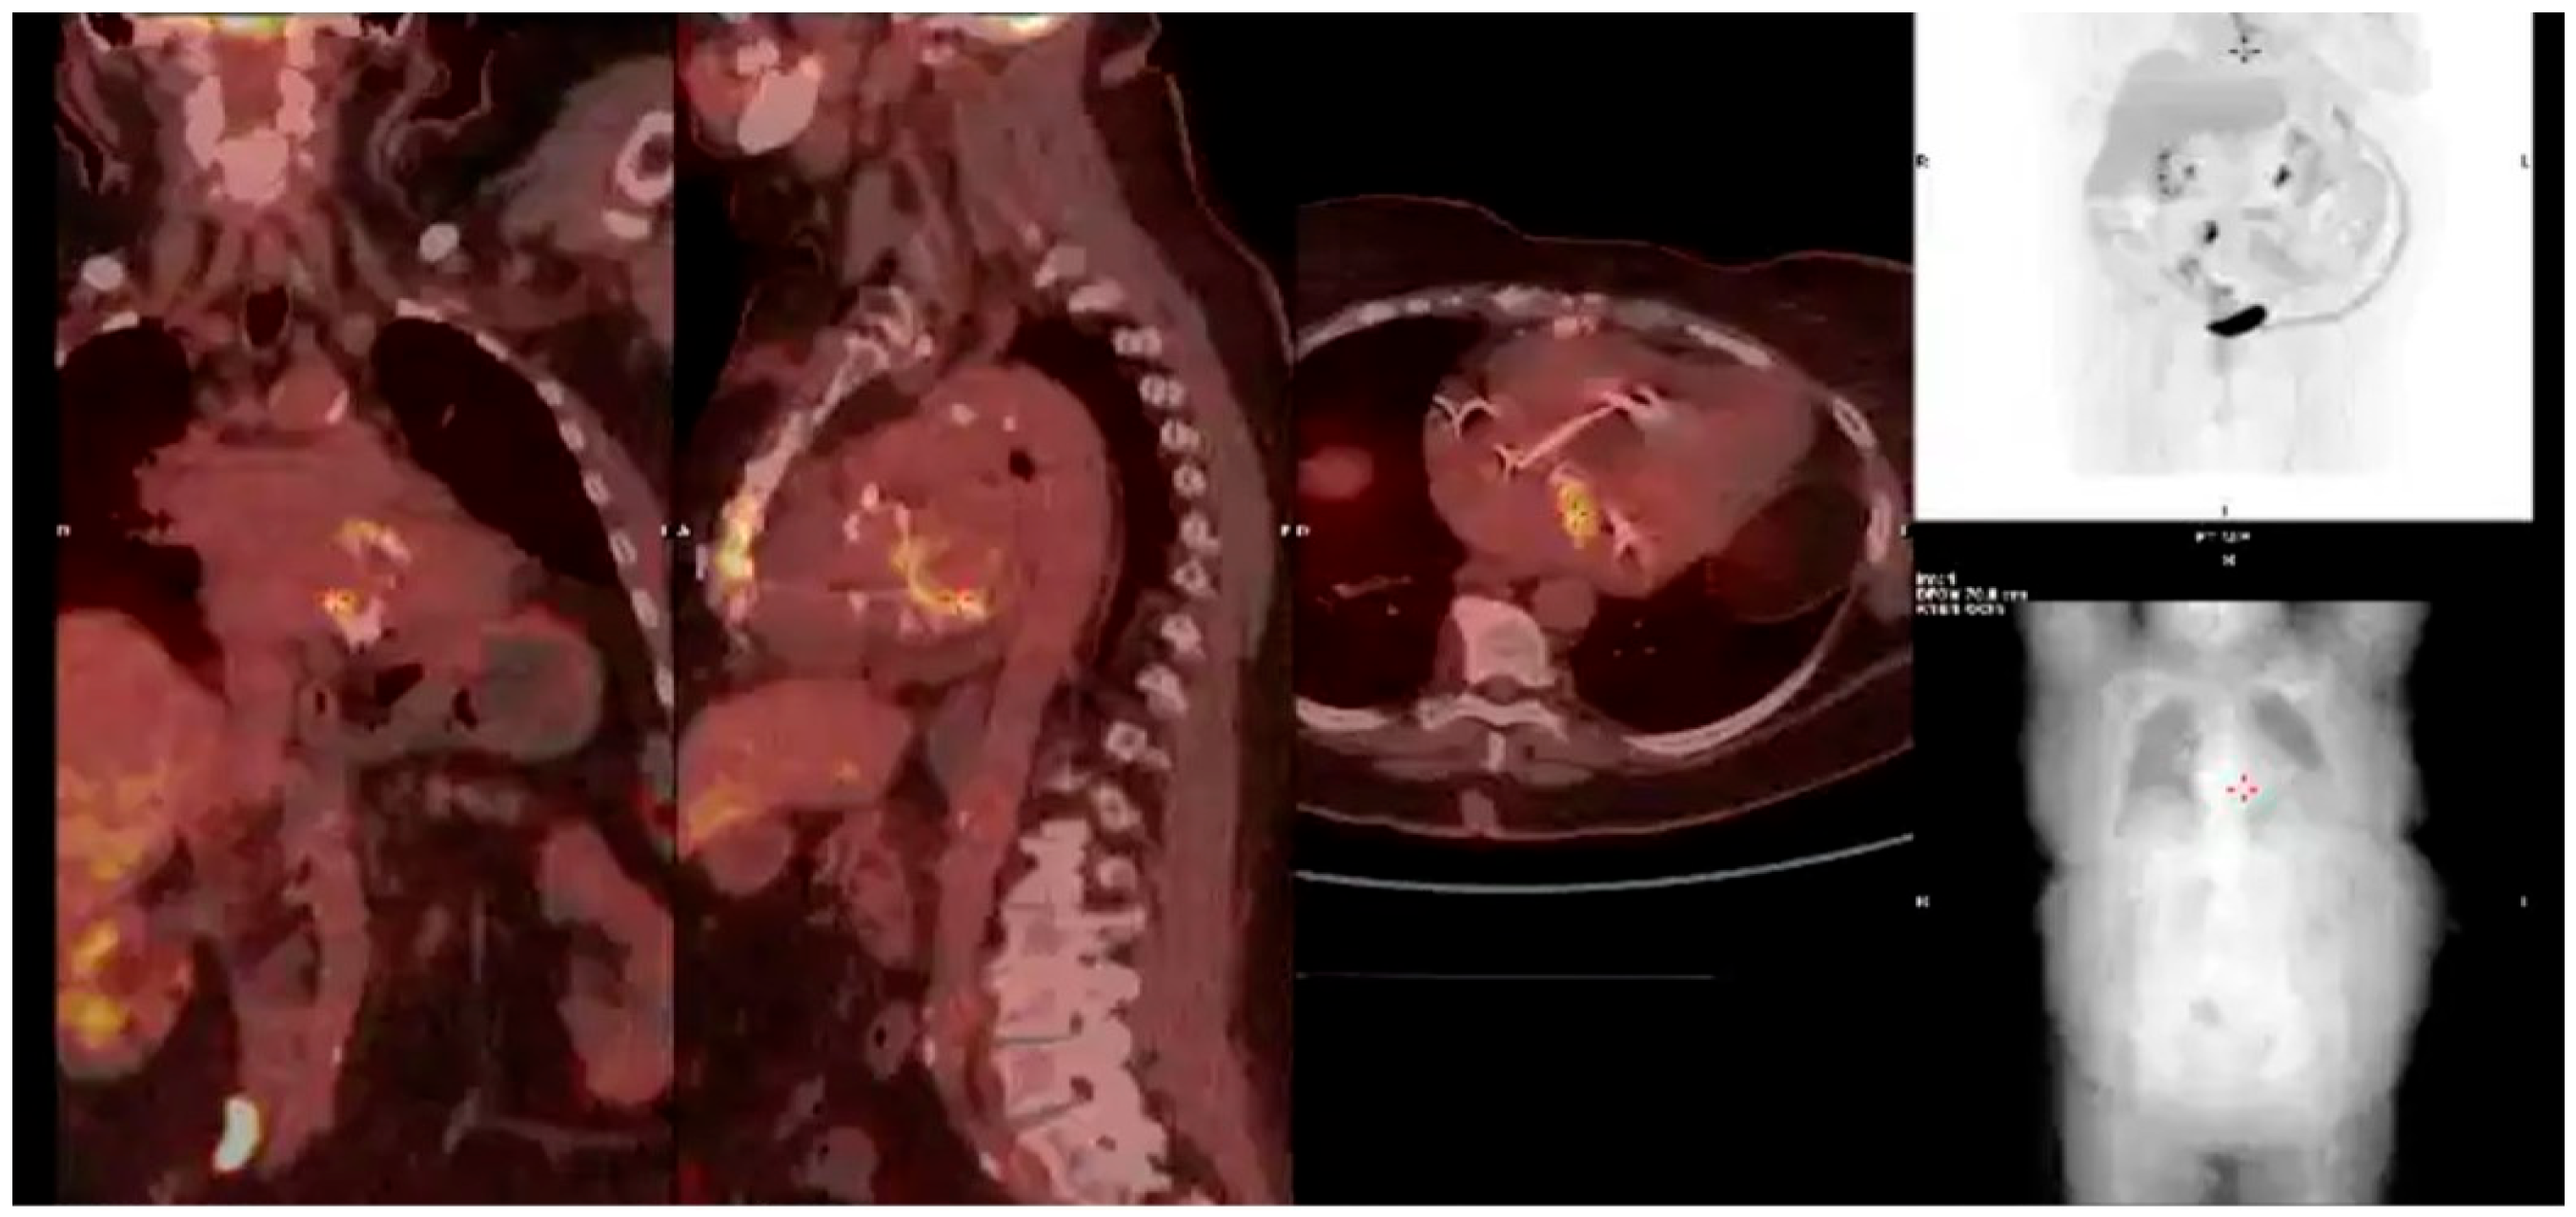

- Prosthetic valve endocarditis (PVE): FDG-PET/CT and WBC scintigraphy are recommended when echocardiography is inconclusive or negative, but clinical suspicion remains high. These modalities are especially valuable for detecting perivalvular infection, invasive complications, and extracardiac septic emboli. Abnormal focal uptake around the prosthesis is considered a significant criterion for PVE diagnosis, and can reclassify cases from “possible” to “definite” IE within the modified Duke criteria framework [13,43,44,45]

- Cardiac device infections: Nuclear imaging is indicated for suspected infection of cardiac implantable electronic devices (CIEDs) when conventional imaging is non-diagnostic. FDG-PET/CT can identify device pocket infection, lead infection, and associated extracardiac complications, and is integrated into the diagnostic algorithm for device-related IE [46]

- Reclassification from possible to definite IE: The ESC guidelines incorporate abnormal FDG-PET/CT or WBC scintigraphy findings as a significant criterion for IE diagnosis in patients with prosthetic valves or devices. This allows for reclassification of cases initially deemed “possible” IE to “definite” IE when nuclear imaging demonstrates focal uptake consistent with infection, particularly in the setting of non-diagnostic echocardiography or ambiguous clinical findings (Figure 16, Figure 17 and Figure 18) [43,44,46].